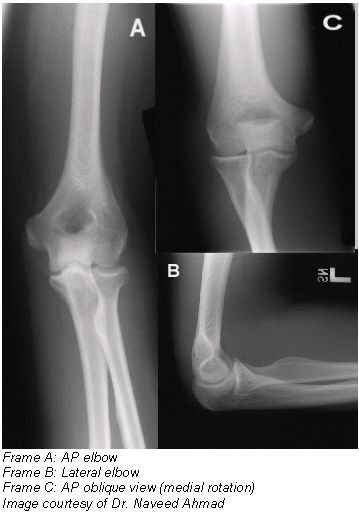

Positioning for an AP oblique projection medial (internal) rotation

- Seat the patient at the end of the radiographic table with the arm extended and in contact with the table.

- Extend the limb in position for an AP projection, and center the midpoint of the cassette to the elbow joint.

- Medially (internally) rotate or pronate (palm-down) the hand.

- Adjust the elbow to place its anterior surface at an angle of 45º (palpating epicondyles to determine a 45º rotation). This degree of obliquity usually clears the coronoid process of the radial head.

- The CR should be perpendicular to the elbow joint.

Evaluation criteria

- Coronoid process in profile should be clearly demonstrated.

- Elongated medial humeral epicondyle.

- Ulna superimposed by the radial head and neck.

- Olecranon process within the olecranon fossa.

- Soft tissue and bony trabeculation visible.

Positioning for an AP oblique projection lateral (external) rotation

- After seating the patient at the end of table, extend the patient's arms into position for an AP projection.

- Center the midpoint of the cassette to the elbow joint.

- Rotate the hand laterally (externally) to place the posterior surface of the elbow at a 45º angle.

- When proper lateral rotation is achieved, the patient’s first and second digits should touch the table.

- An oblique view of the distal humerus and proximal radius and ulna should be demonstrated.

- Correct 45º lateral oblique should project the radial head, neck, and tuberosity, free of superimposition by ulna.

- Open elbow joint should be clearly demonstrated.

- Soft tissue and bony trabeculation should be visible.